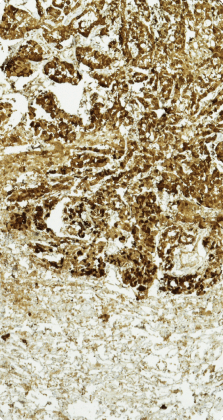

The diagnosis of ovarian mesothelioma should be confirmed via immunohistochemical staining. This is the most reliable means to distinguish ovarian mesothelioma cells from ovarian cancer cells.